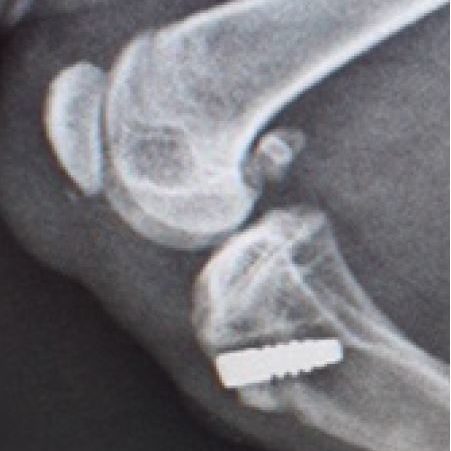

Patellar Tendon reconstruction Under Construction. Share this post Share on FacebookShare on Facebook TweetShare on Twitter Pin itShare on Pinterest Share on LinkedInShare on LinkedIn Share on WhatsAppShare on WhatsApp Project navigationPreviousPrevious project:CarpusNextNext project:Minimally invasive Extra-articular CCL Repair